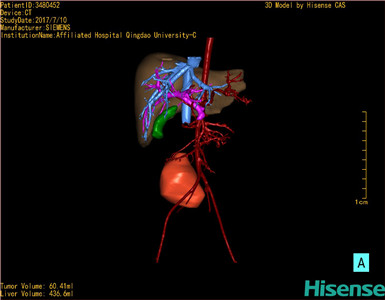

通过调节窗宽窗位调整CT序号,对肿瘤,肝实质,胆囊,下腔静脉,肿瘤,肝动脉、门静脉及肝静脉等进行三维重建;系统自动计算肿瘤体积和肝脏体积。模拟手术操作,自动计算切除肿瘤体积。肝脏体积为436.6ml,肿瘤体积为60.41ml,与血管联系紧密,术前手术方案的规划。

术前三维重建:

重建图片